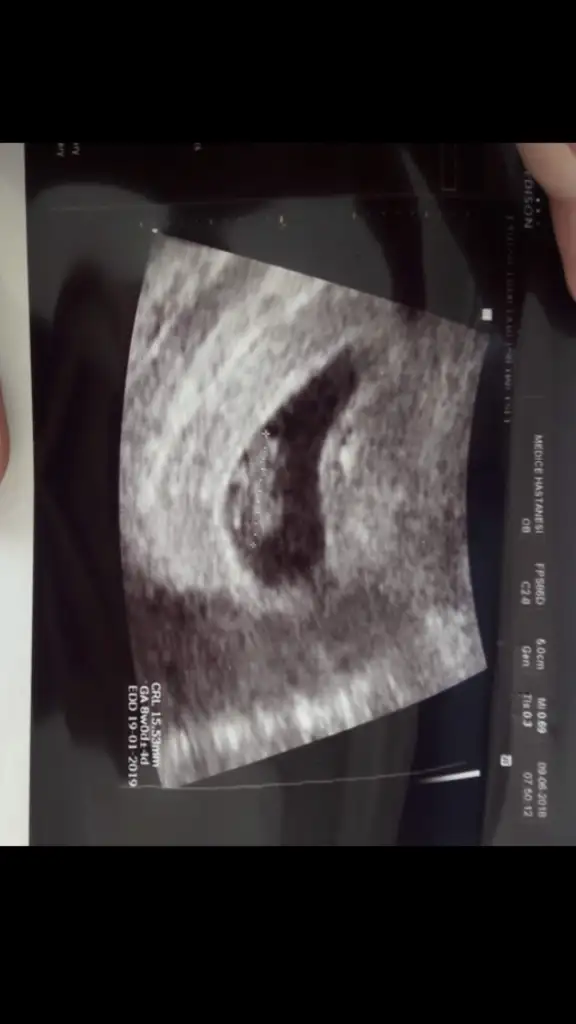

Kızlarr iyi geceler ❤️ Son adet tarihim 1 ocaktı. Bugün ilk kez doktora gittim. Keseyi ve bebişi gördü, kalp atışını da kuvvetlice duyduk çok şükür 🥰 SAT'a göre 6+6 olmalıydı bebeğim fakat boyunu ölçünce 7+4 çıktı, kese ölçümüne göre de 8+3 dedi doktor. Şükür kese çevresinde kanama vs yokmuş her şey yolunda dedi 🤲 1 ay sonra çağırdı kontrole, bir aksilik olmazsa 5 hafta sonra giderim muhtemelen hem ikili tarama testi yapılır diye düşünüyorum.